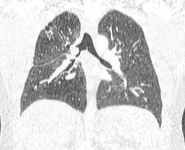

Malignant endobronchial obstruction on multidetector chest CT: coronal reconstruction demonstrating right mainstem malignant obstruction

From the collections of Jose Fernando Santacruz MD, FCCP, DAABIP and Erik Folch MD, MSc; used with permission